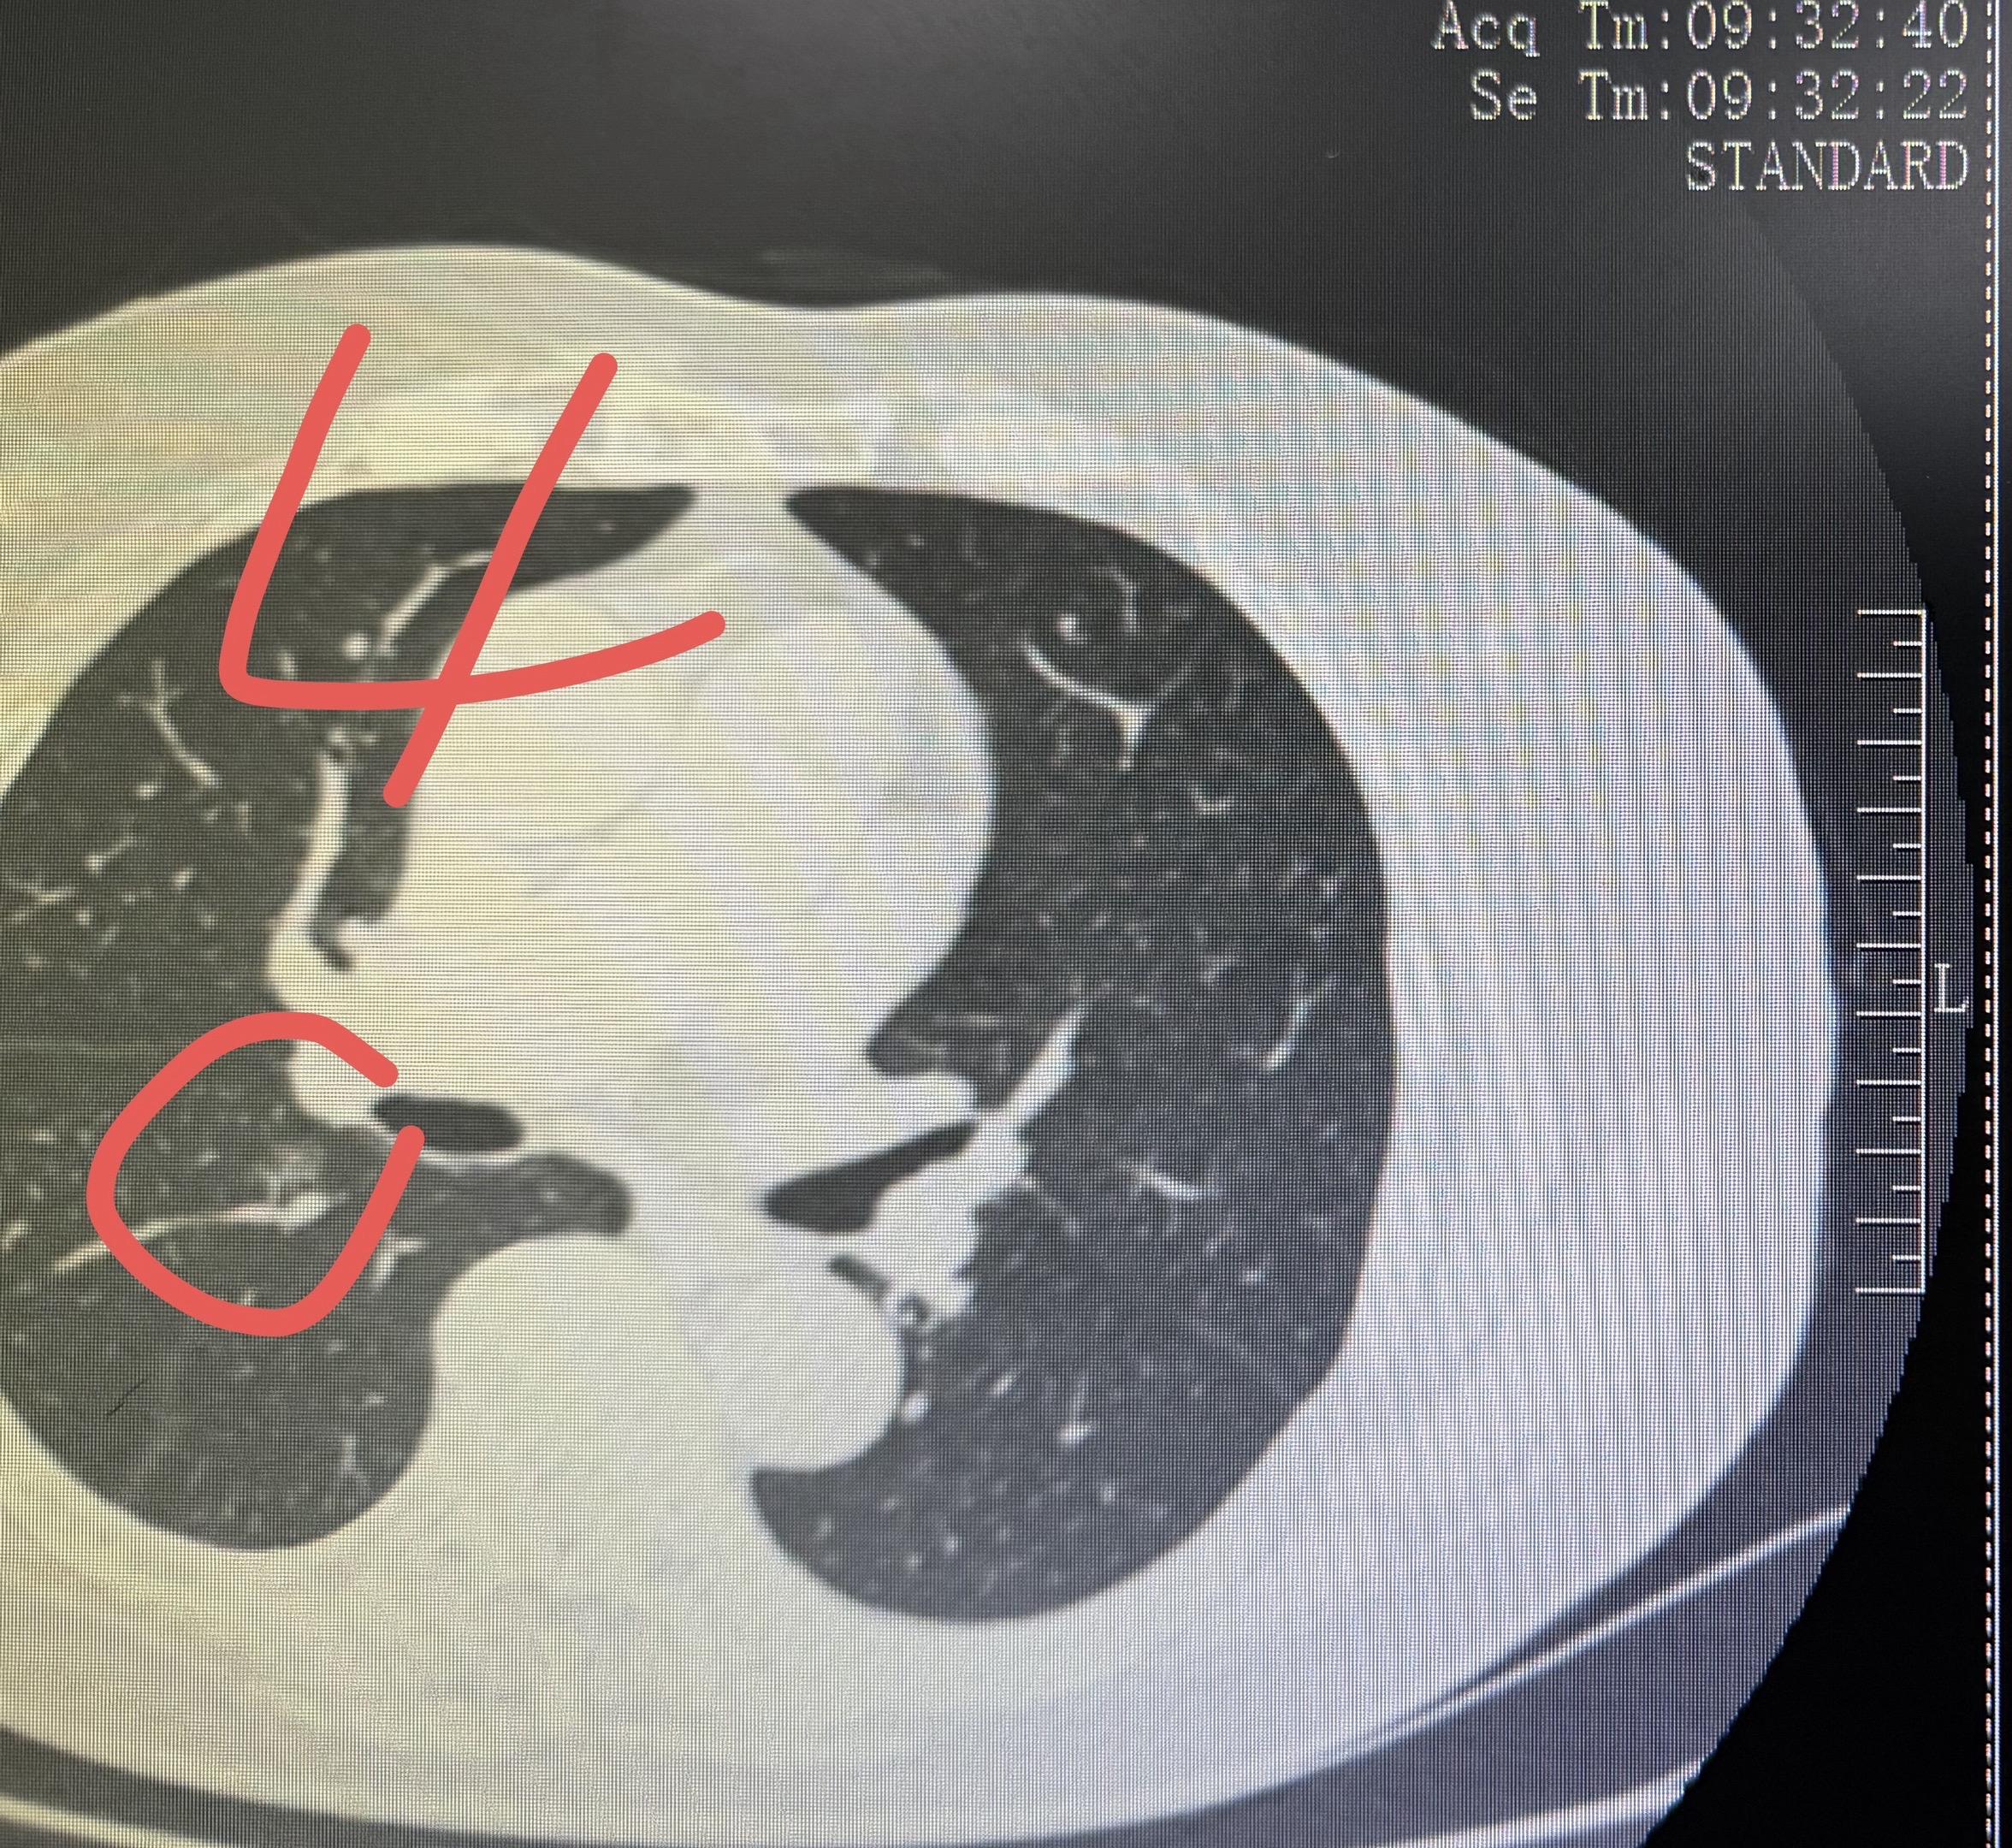

分享一个80岁多发结节的案例!如何治疗结。这个婆婆有4个有癌性磨玻璃结节,左侧两个1和2,右侧两个3和4。我们左侧做了腔镜楔形切除,术后病理浸润性腺癌,术后辅以治疗。右侧这两个结节在术后保守观察的过程中,明显缩小消失,应该是我们的术后辅助治疗起了作用。这就是,用一套治疗方案,解决了4个磨玻璃结节,该切的切,该保守的保守,病人损失最小化!